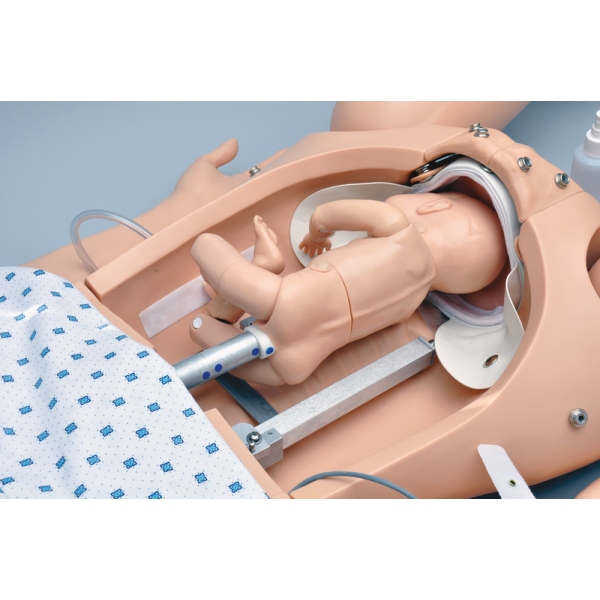

Noelle Simulator poroda mater in novorojenčkov

Zasnovan tako, da zagotavlja popolno porodno izkušnjo pred, med in po porodu.

- avtomatski porodni sistem

- en premikajoč se porodni otrok s posteljico